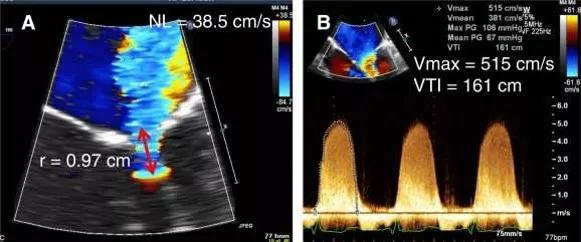

超声心动图十大基本功8.1:超声心动图评估瓣膜返流的常用方法